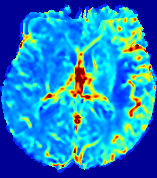

LesionRefer to captionRefer to captionRefer to captionRefer to captionRefer to captionRefer to caption𝐕rgbsubscript𝐕𝑟𝑔𝑏{\bf{V}}_{rgb}Refer to captionRefer to captionRefer to captionRefer to captionRefer to captionRefer to caption𝐕2subscriptnorm𝐕2{\|\bf{V}}\|_{2}Refer to captionRefer to captionRefer to captionRefer to captionRefer to captionRefer to captionRefer to caption3.53.53.52.82.82.82.12.12.11.41.41.40.70.70.70.00.00.0(mm/s)𝑚𝑚𝑠(mm/s)D𝐷DRefer to captionRefer to captionRefer to captionRefer to captionRefer to captionRefer to captionRefer to caption0.0200.0200.0200.0160.0160.0160.0120.0120.0120.0080.0080.0080.0040.0040.0040.0000.0000.000(mm2/s)𝑚superscript𝑚2𝑠(mm^{2}/s)Slice #1Slice #2Slice #3Slice #4Slice #5Slice #6

Figure 3: PIANO feature maps for one stroke patient, where the lesion is located in the left hemisphere. Top row: segmented stroke lesion region (white) on different slices, obtained from ISLES 2017. The corresponding slices for the PIANO feature maps are shown in the following rows.

For a better insight into an estimated velocity field 𝐕𝐕{\bf{V}} and diffusion field 𝐃𝐃{\bf{D}}, we compute the following maps: (1) 𝐕rgbsubscript𝐕𝑟𝑔𝑏{\bf{V}}_{rgb}: Color-coded orientation map of 𝐕=(Vx,Vy,Vz)T𝐕superscriptsuperscript𝑉𝑥superscript𝑉𝑦superscript𝑉𝑧𝑇{\bf{V}}=(V^{x},V^{y},V^{z})^{T}, obtained by normalizing 𝐕𝐕{\bf{V}} to unit length and mapping its 3 components to red, green, blue respectively; (2) 𝐕2subscriptnorm𝐕2\|{\bf{V}}\|_{2}: 222 norm of 𝐕𝐕{\bf{V}}; (3) D𝐷D: scalar field in Eq. 5.

Fig. 3 and Fig. 4 show the PIANO feature maps estimated from two ISLES 2017 patients: all are highly consistent with the lesion in both cases. Details of the blood flow trajectories are revealed in 𝐕rgbsubscript𝐕𝑟𝑔𝑏{\bf{V}}_{rgb} by the ridged patterns and the sharp changes of colors in the unaffected (right) hemisphere, while the flat patterns appearing within the lesion provide little directional information about the velocity and indicate low velocity magnitudes. Velocity magnitudes are more directly visualized via 𝐕2subscriptnorm𝐕2\|{\bf{V}}\|_{2}, from which one can easily locate the lesion where 𝐕2subscriptnorm𝐕2\|{\bf{V}}\|_{2} is low. D𝐷D also indicates lower diffusion values in the lesion, though with less contrast potentially due to the fact that it captures the accumulated effect of CA diffusion at the voxel-level.